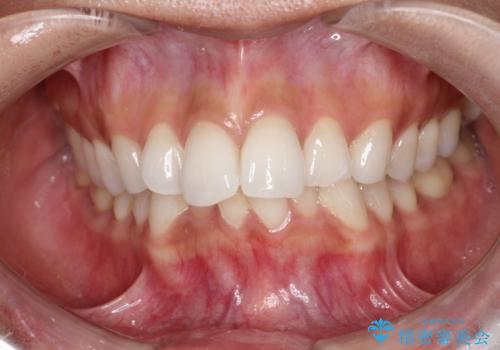

【インビザライン】前歯の凸凹をIPRで改善

- 前歯の凸凹を主訴に来院されました。

前歯を並べるために歯と歯の間にヤスリを入れてわずかに歯を削ることでスペースを確保しています。

歯と歯の間にヤスリを入れてわずかに歯を削ることでスペースを確保する処置をIPRと呼びます。

当院では拡大鏡を用いて丁寧に処置することで歯冠形態を損なわずに行うことができます。